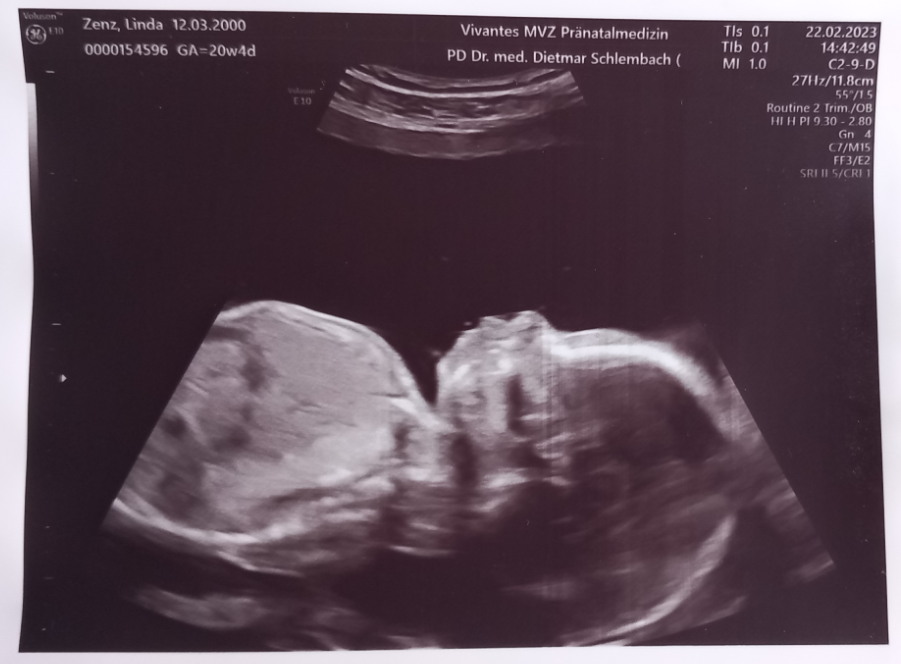

Wenn das ungeborene Kind an einer Zwerchfellhernie leidet, ist das immer auch eine große Belastung für die Eltern. Ich musste das zusammen mit meiner Frau Linda leider am eigenen Leib erfahren. Ende 2022 wurde meine Frau zum zweiten Mal schwanger. Im Februar 2023 - der 20. Schwangerschaftswoche - wurde bei der Feindiagnostik ein Problem festgestellt: das Herz unseres Kindes befand sich nicht an der richtigen Stelle. Für uns und die Ärztin war die Ursache zu diesem Zeitpunkt überhaupt nicht klar. Die einzige Gewissheit, die wir hatten, war die, dass es ein Problem gab. Wir waren am Boden zerstört, wie konnte das sein? Wir waren jung und gesund, wieso passierte uns so etwas?

Unsere Ärztin organisierte so schnell wie möglich einen Untersuchungstermin mit präziseren Geräten und so saßen wir zwei Tage später bei Herrn Dr. Dietmar Schlembach in der Klinik für Geburtsmedizin des Vivantes Klinikum Neukölln.

Er stellte fest, dass unser Kind - ein Mädchen - an einer rechtsseitigen Zwerchfellhernie leide.

Ultraschall Enya im Ultraschall

Wir hatten an diesem Tag und auch an allen weiteren Terminen sehr viele Fragen und Dr. Schlembach nahm sich stets die Zeit, alle unsere Fragen zu beantworten. Und weitere Termine gab es viele: Bei Dr. Schlembach waren wir anfangs alle vier Wochen, später alle zwei. Insgesamt waren wir bis zur Geburt sechs Mal dort, wobei es sich wie dutzende Male anfühlte. Uns wurde erklärt, dass die Geburt nicht in unserem nächstgelegenen Krankenhaus stattfinden kann, sondern in Neukölln stattfinden muss. Es musste nämlich nach der Geburt eine OP durchgeführt werden, bei der die in den Brustkorb gerutschte Leber in den Bauchraum zurück geschoben und das Zwerchfell verschlossen wird. Mit etwas Pech könnten auch mehrere OPs notwendig werden. Im schlimmsten Fall müsste die Geburt in Mannheim durchgeführt werden, weil die Ärzte dort für den absoluten Notfall die ECMO-Therapie anwenden können. Wir könnten uns auf jeden Fall dazu entscheiden, sollte uns das lieber sein, Dr. Schlembach sah dazu allerdings keinen Anlass. Auf jeden Fall würden aber im Laufe von Enyas Leben viele Nachuntersuchungen stattfinden und vielleicht auch noch Jahre später Korrekturoperationen notwendig werden.